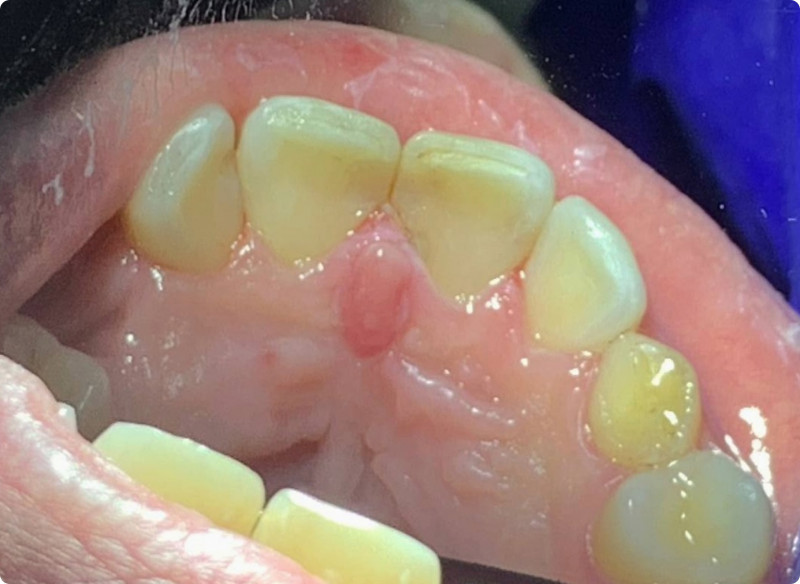

На странице представлено портфолио стоматологий Красноярска с работами до и после профессиональной чистки зубов. В нашем портфолио собраны разные клинические случаи: от удаления незначительного налета до снятия массивного поддесневого камня. Здесь вы можете увидеть, как возвращается естественный цвет и внешний вид зубов после процедуры. Изучите результаты до и после чистки зубов, чтобы увидеть реальный эффект и выбрать клинику в Красноярске, где профессиональная гигиена поможет вернуть зубам здоровый вид.

Профгигиена